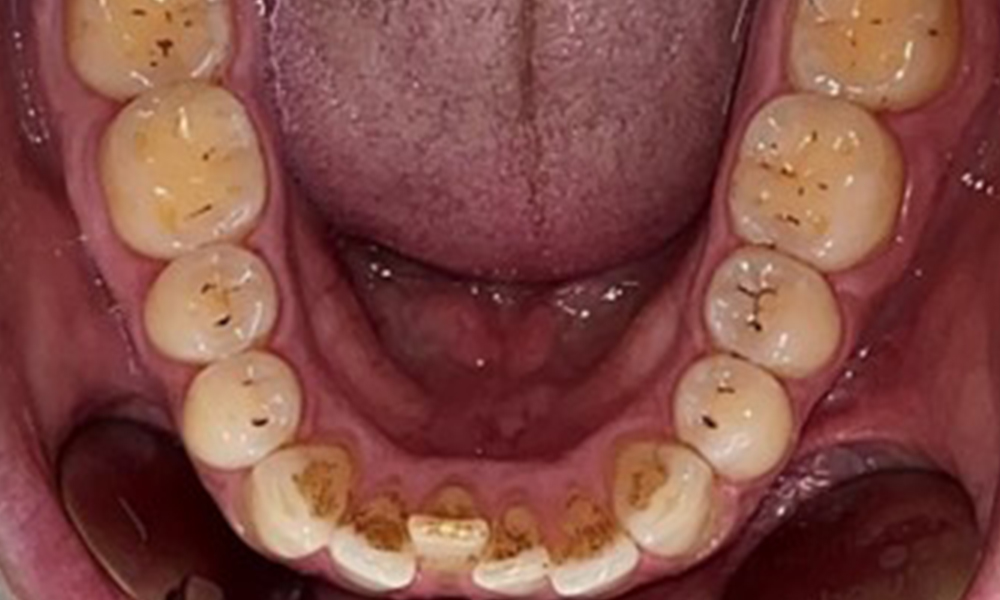

Дентални резултати

Пациентът има пълно съзъбие с общо 28 зъба. Налице са забележими ерозии и атриции. (Фиг. 4, Фиг. 5). Поради бруксизъм пациентът е носил шина с коригиран блок на захапката през нощта в продължение на много години. Ерозиите са причинени от продължителна консумация на изотонични напитки. Не сe наблюдава загуба на пародонтална кост или активни кариозни лезии.